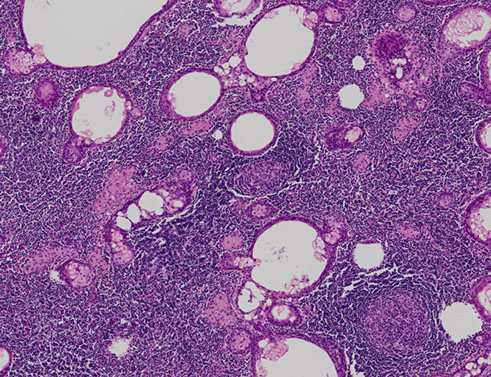

Papillary Cystadenoma Lymphomatosum (Warthin tumor)

2nd MC salivary gland tumor (~10% overall salivary gland tumors)

- MC in male smokers over 50 yo, bilateral (in 1/20?)

- arises from lymph tissue w/in parotid gland and is usually multifocal

Gross: filled c grumous material (from cysts)

Micro: Double layer composed of outer columnar cells and inner cuboidal cells lining reactive (not neoplastic) lymphoid tissue [comes from native lymph tissue of parotid]

- outer layer filled with mitochondria and appears reddish (termed "oncocytic"); the outer epithelial layers are the neoplastic component of Warthin's

- may infarct if becomes too big and have central necrosis

- deprive oncocytes of O2 a little bit and they will infarct, so watch out for reactive changes

- can have "motor oil" background cytologically

***WAR THE NODE (lymph node, that is)***

- WarthiN looks like a lymph Node

Tx: Superficial parotidectomy

- may infarct if untx'd

Px: may rarely transform into a higher-grade tumor

Warthin tumor